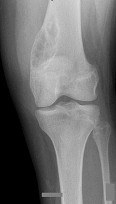

Question 18

A 60-year-old male presents with isolated medial compartment knee osteoarthritis and is being evaluated for a unicompartmental knee arthroplasty (UKA). According to classical indications (Kozinn and Scott), which of the following is considered an absolute contraindication to a fixed-bearing UKA?

Explanation

Classical criteria for unicompartmental knee arthroplasty (UKA) include an intact anterior cruciate ligament (ACL). ACL deficiency leads to altered knee kinematics, specifically paradoxical anterior translation of the tibia during flexion, which results in accelerated posterior polyethylene wear and early failure of a fixed-bearing UKA. While some modern surgeons perform UKA in ACL-deficient knees using mobile-bearing designs or concurrent ACL reconstruction, an absent ACL remains a classic board-tested contraindication for standard UKA.